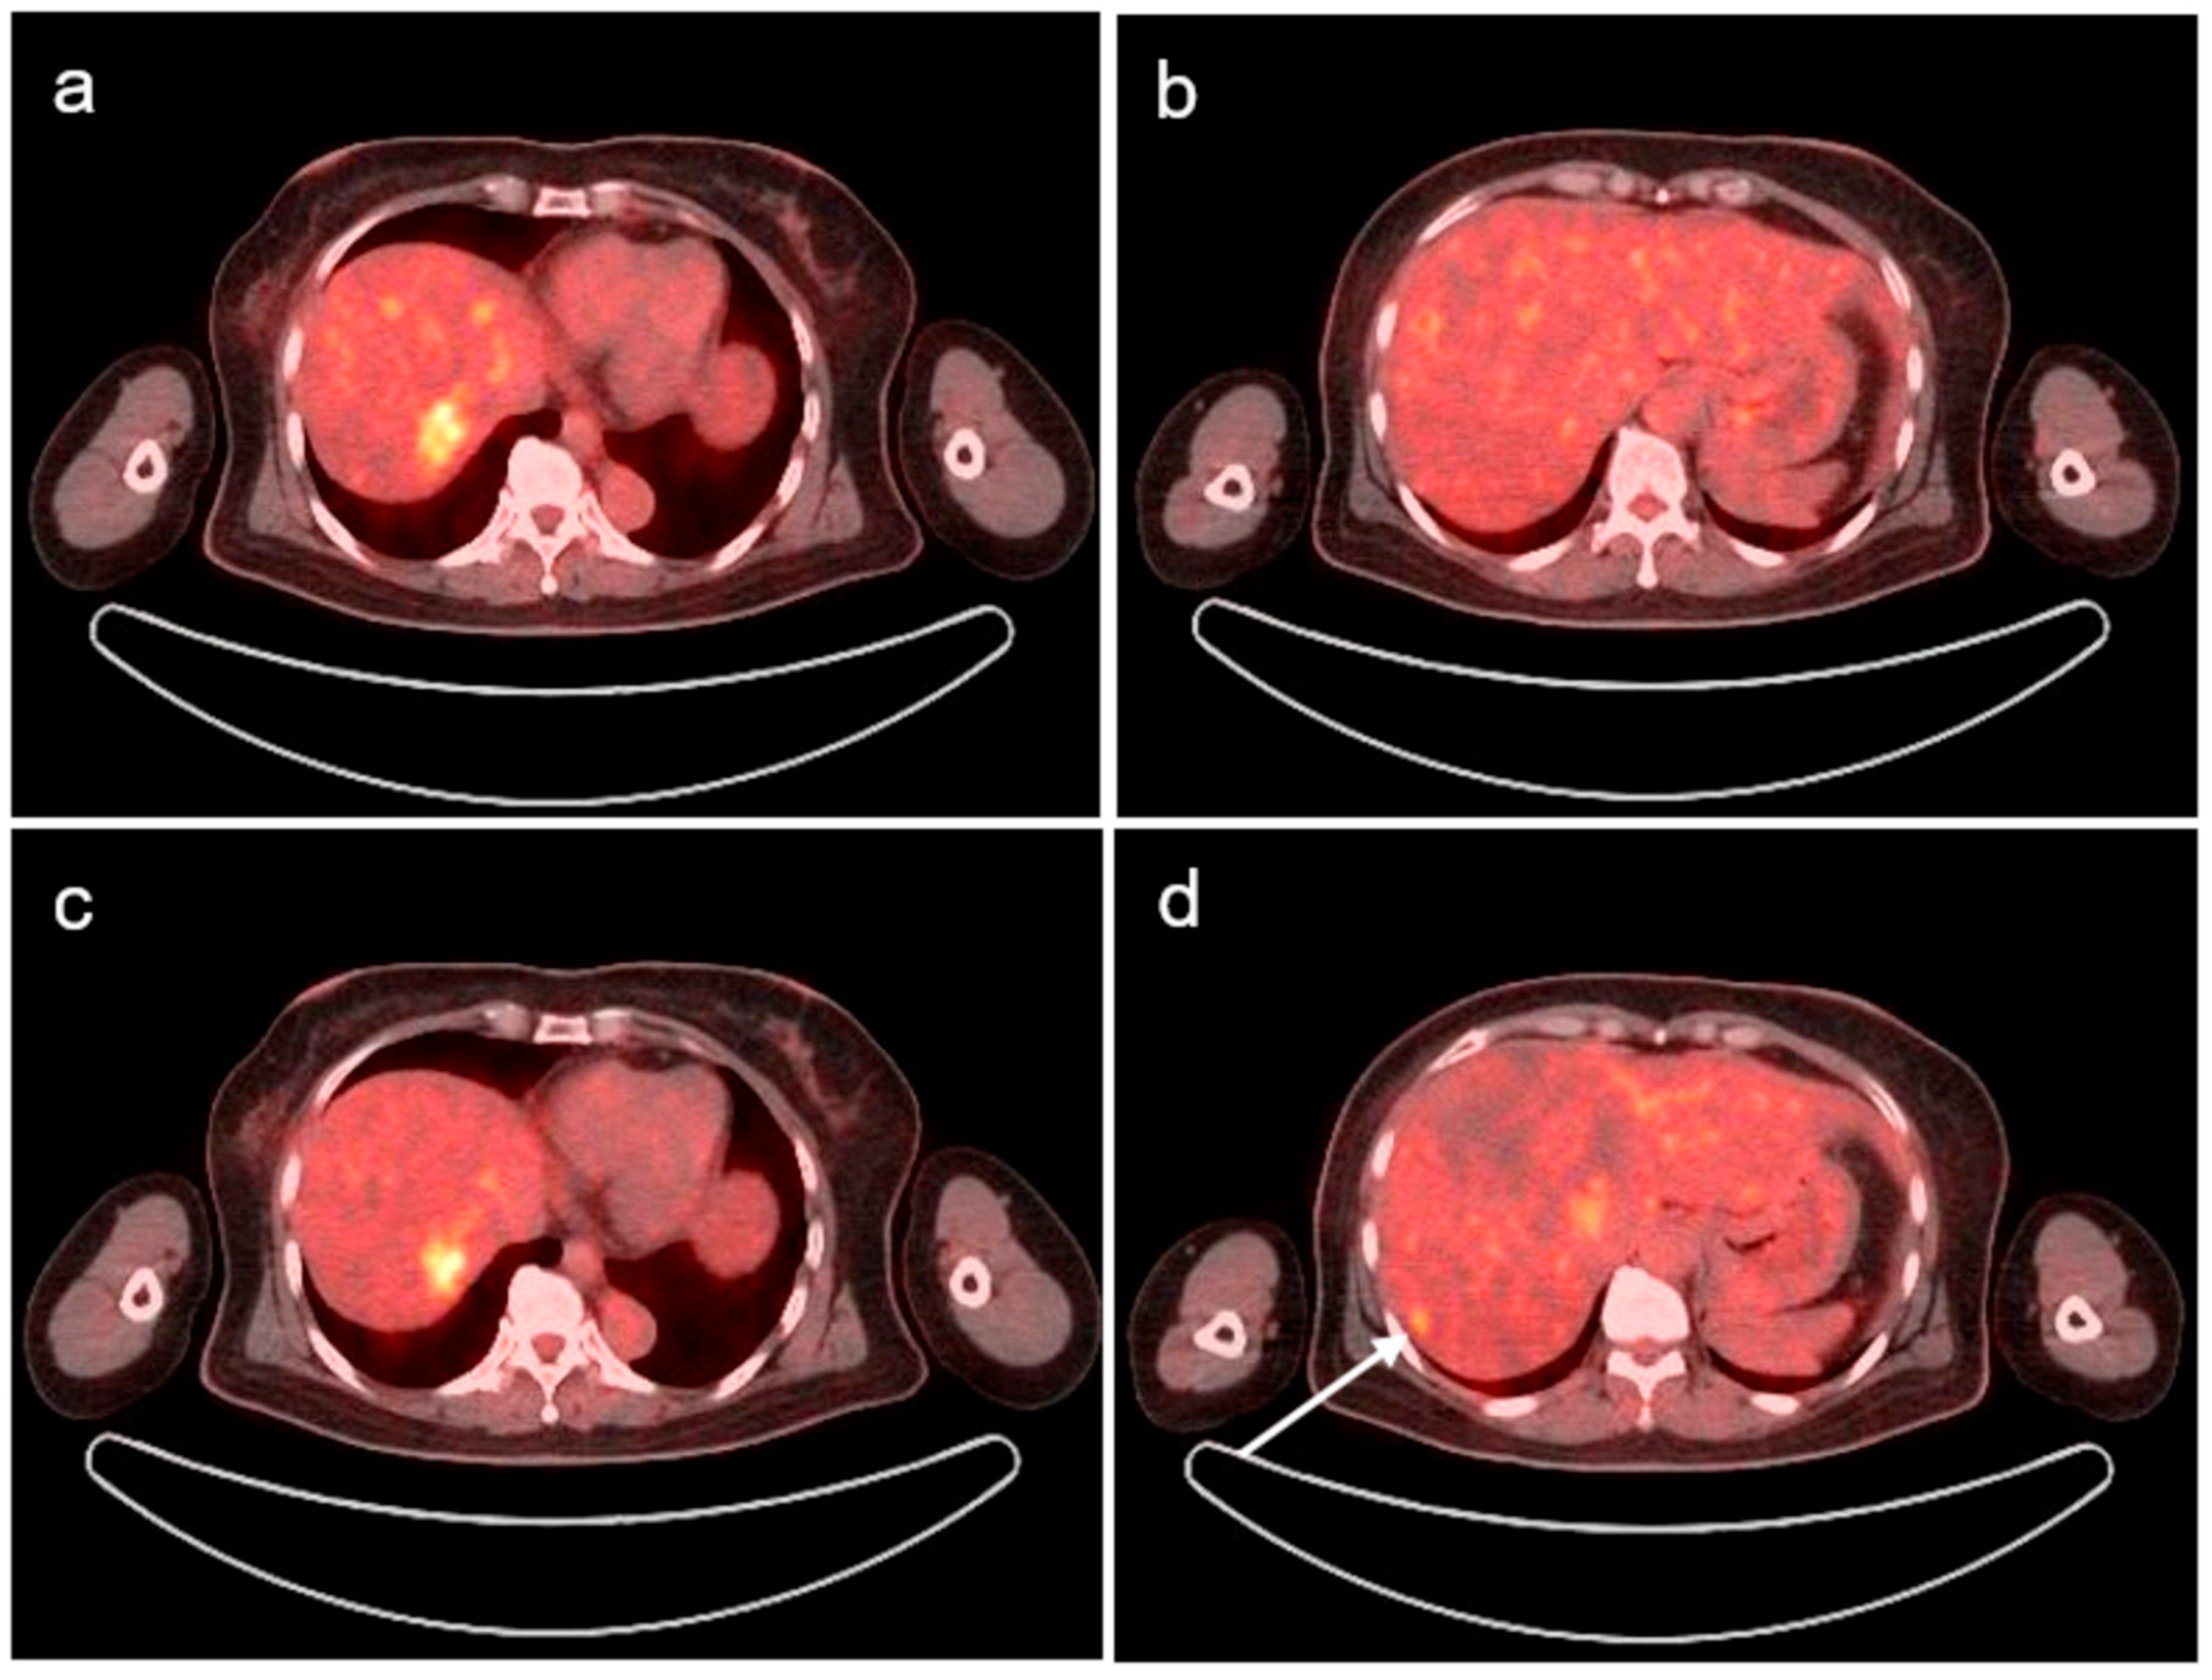

Detection of Hepatic Metastasis from Early Delayed Images of Modified Dual-Time-Point F-18 FDG PET/CT Images in a Patient with Breast Cancer